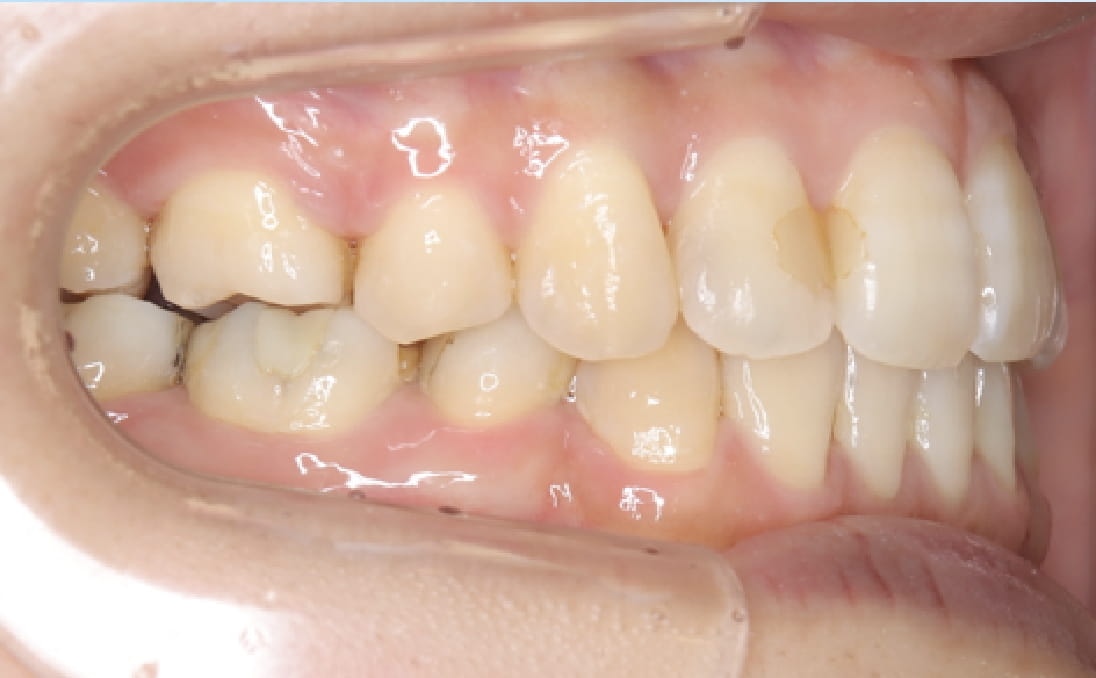

《叢生(デコボコ)を伴う上下顎前突》

症例1

性別:女性 年齢:19歳 お住まいの地域:奈良市

主訴 前歯のガタガタと出っ歯

治療装置 白い表側矯正装置

抜歯 4本の抜歯

治療期間 2年2ヶ月

診断名 歯槽性上下顎前突

副作用 歯肉退縮・歯根吸収・歯髄・壊死・癒着による予期せぬ歯の動き

上下の歯の前歯の角度が傾斜しているため、抜歯が必要なケースでした。

上下の前突感を可能な限り後ろに下げました。

治療前